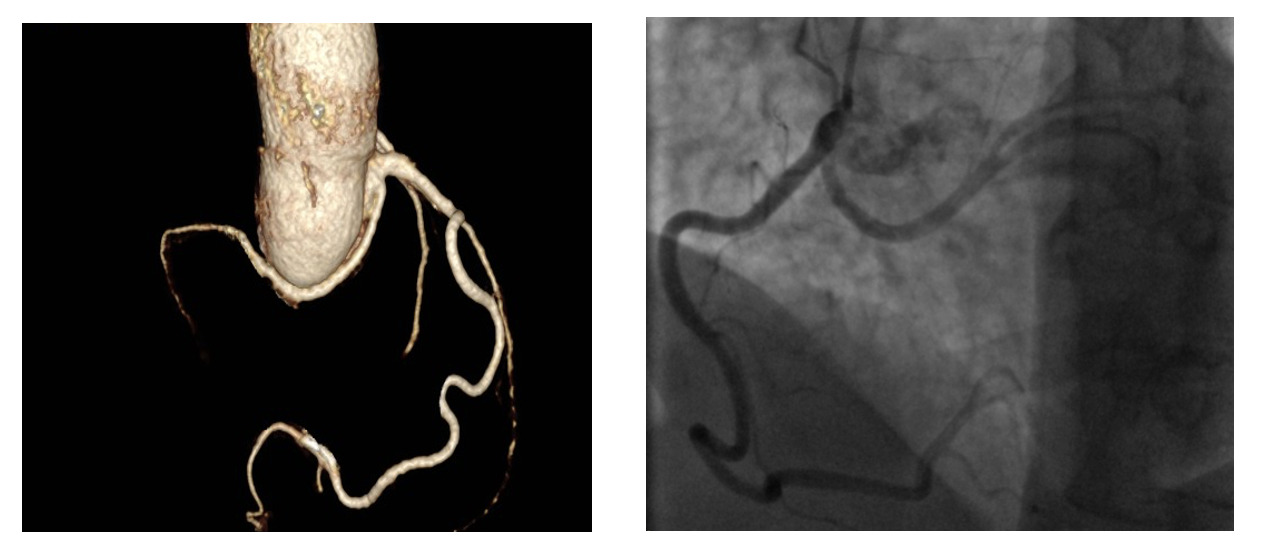

A 45-year-old male (height 168 cm, weight 95 kg, body mass index 33.7, body surface area 2.04 m2) with chest pain was admitted via ambulance to the clinic at his place of residence. During the examination, the patient had a paroxysm of ventricular tachycardia, stopped by medication. According to the ECG data, signs of hypertrophy of the left ventricle (LV) with subepicardial damage to its anterior parts were revealed. After performing thrombolysis (Actilyse (Boehringer ingelheim pharma, GmbH & Co.KG, Germany) 100 mg for 90 minutes), the patient was transferred to our Center for the further treatment. At the time of admission, there was a significant elevation of troponin I levels to 101 ng / ml with progressive decreasing in the follow. Coronary angiography showed no hemodynamically significant stenosis of the coronary arteries, but an anomalous origin of the left circumflex artery from the RCA was noted (Fig.1B). Myocardial injury was regarded as a type 2 myocardial infarction due to ventricular tachycardia paroxysm. Echocardiography revealed severe aortic stenosis with an aortic valve area 0.88 cm², a peak acceleration of blood flow of 4.2 m/s, an average pressure gradient of 42 mmHg, and the diameter of the AV fibrous ring 21 mm. LV hypertrophy was noted: posterior and interventricular septum of 18 and 15, respectively. Also, no regional areas of contractility disorders were noted. Taking into account the acute stage of type 2 myocardial infarction and severe aortic stenosis surgical treatment were postponed for 4-6 weeks. During rehospitalization for the surgical treatment CTA was performed to clarify the anatomical features of the aortic root and coronary arteries (Fig.1A).

An anomalous origin of the left circumflex artery from the right sinus of Valsalva or right coronary artery with a retroaortic course is a known coronary anomaly that usually does not cause clinical symptoms.5 In patients with AOLCx the risk of myocardial ischemia due to insufficient myocardial protection and compression by the valve prosthesis ring of anomalous LCx increases during AVR.5 To prevent possible complications due to traumatization of anomalously located LCx when stitching the fibrous ring of the aortic valve. Additional imaging methods should be used for assessing the anatomy of the aortic root and coronary bed. In our case, CTA with three-dimensional reconstructions of aorta and coronary arteries (Fig.1 A.), as a minimally invasive and maximally informative research method, was the most preferable diagnostic tool. In cases where the abnormal LCx originating from the RCA is located retroaortically, it is necessary to take into account its possible ligation during stitching of the fibrous ring of the aortic valve and/or its compression by the ring (sewn cuff) of the prosthesis after implantation of the latter in the AV position.5 Some authors recommend implantation of smaller prosthesis in such cases.6 However, in our case, taking into account the ratio of diameter of the fibrous ring of aortic valve and the surface area of the patient’s body, implantation of a small prosthesis would inevitably entail the development of a patient-prosthetic discrepancy, and therefore it was decided to implant an aortic prosthetic valve with preliminary mobilization of abnormal LCx and performing aortic root enlargement by Nicks. The mobilization of abnormal LCx provided us full control during the aortic root enlargement and stitching of the fibrous ring of the AV, as well as the opportunity to assess the compression of the artery after implantation of the prosthesis. Our case is unique in that it illustrates the possible AVR with a prosthesis of optimal size with preliminary mobilization of the abnormal artery and aortic root enlargement. The successful outcome in this case was the result of preoperative imaging techniques, which made it possible to assess the anatomical features of the abnormally formed coronary bed and the relationship between the coronary arteries and the structures of the aortic root. In cases where the mobilization of abnormal LCx is technically impossible for the prevention of myocardial damage during AVR and/or MVR coronary artery bypass surgery of the abnormal arteries is the method of choice, however, this provision requires additional research.6